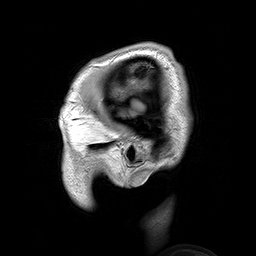

MRI ראש | אנימציה: דווין ריד; לקוח מוויקיפדיה

ההדמיה הפונקציונלית, באמצעות דימות תהודה מגנטית תפקודי (fMRI), מתבססת על ההבדל בין התהודה המגנטית של דם מחומצן לבין זה של דם לא מחומצן. ההדמיה בשיטה הזו מזהה בזמן אמת אלו חלקים במוח נוטלים חלק בפעילויות מחשבתית כגון קריאה או שינון, על ידי מיפוי זרימת הדם המחומצן אליהם. לדוגמה, אם מבנים, תבניות או תהליכים ספציפיים במוח פעילים בזמן שאנו שומעים את התקליט האחרון של הראפר קניה וסט, משננים חומר למבחן או סתם מדמיינים משהו להנאתנו, אזורים מסוימים במוח "יידלקו" על מסכי מכשיר ההדמיה וילמדו איזה מבנים ואיזה תהליכים במוח מעורבים בפעולה הקוגניטיבית הזו. כך אפשר ללמוד רבות על מעורבותם של חלקים שונים במוח בתהליכי המחשבה השונים.

דימות המוח ב-fMRI מהקודקוד עד בסיס הגולגולת | אנימציה: ויקיפדיה